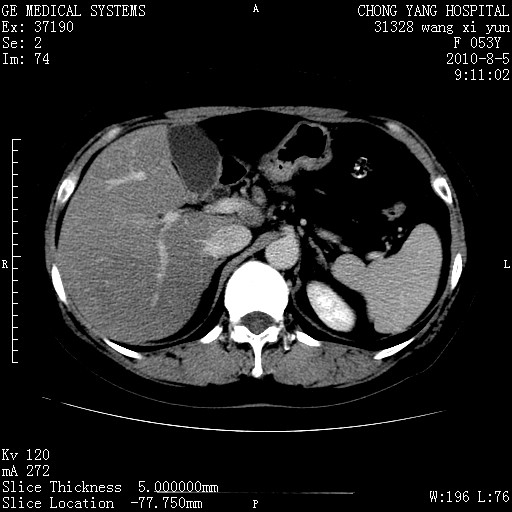

标题: CT28214:F41Y 血尿二十天,建议盆腔平扫加增强。

1)考虑肝左叶胆管细胞癌。2)脂肪肝。